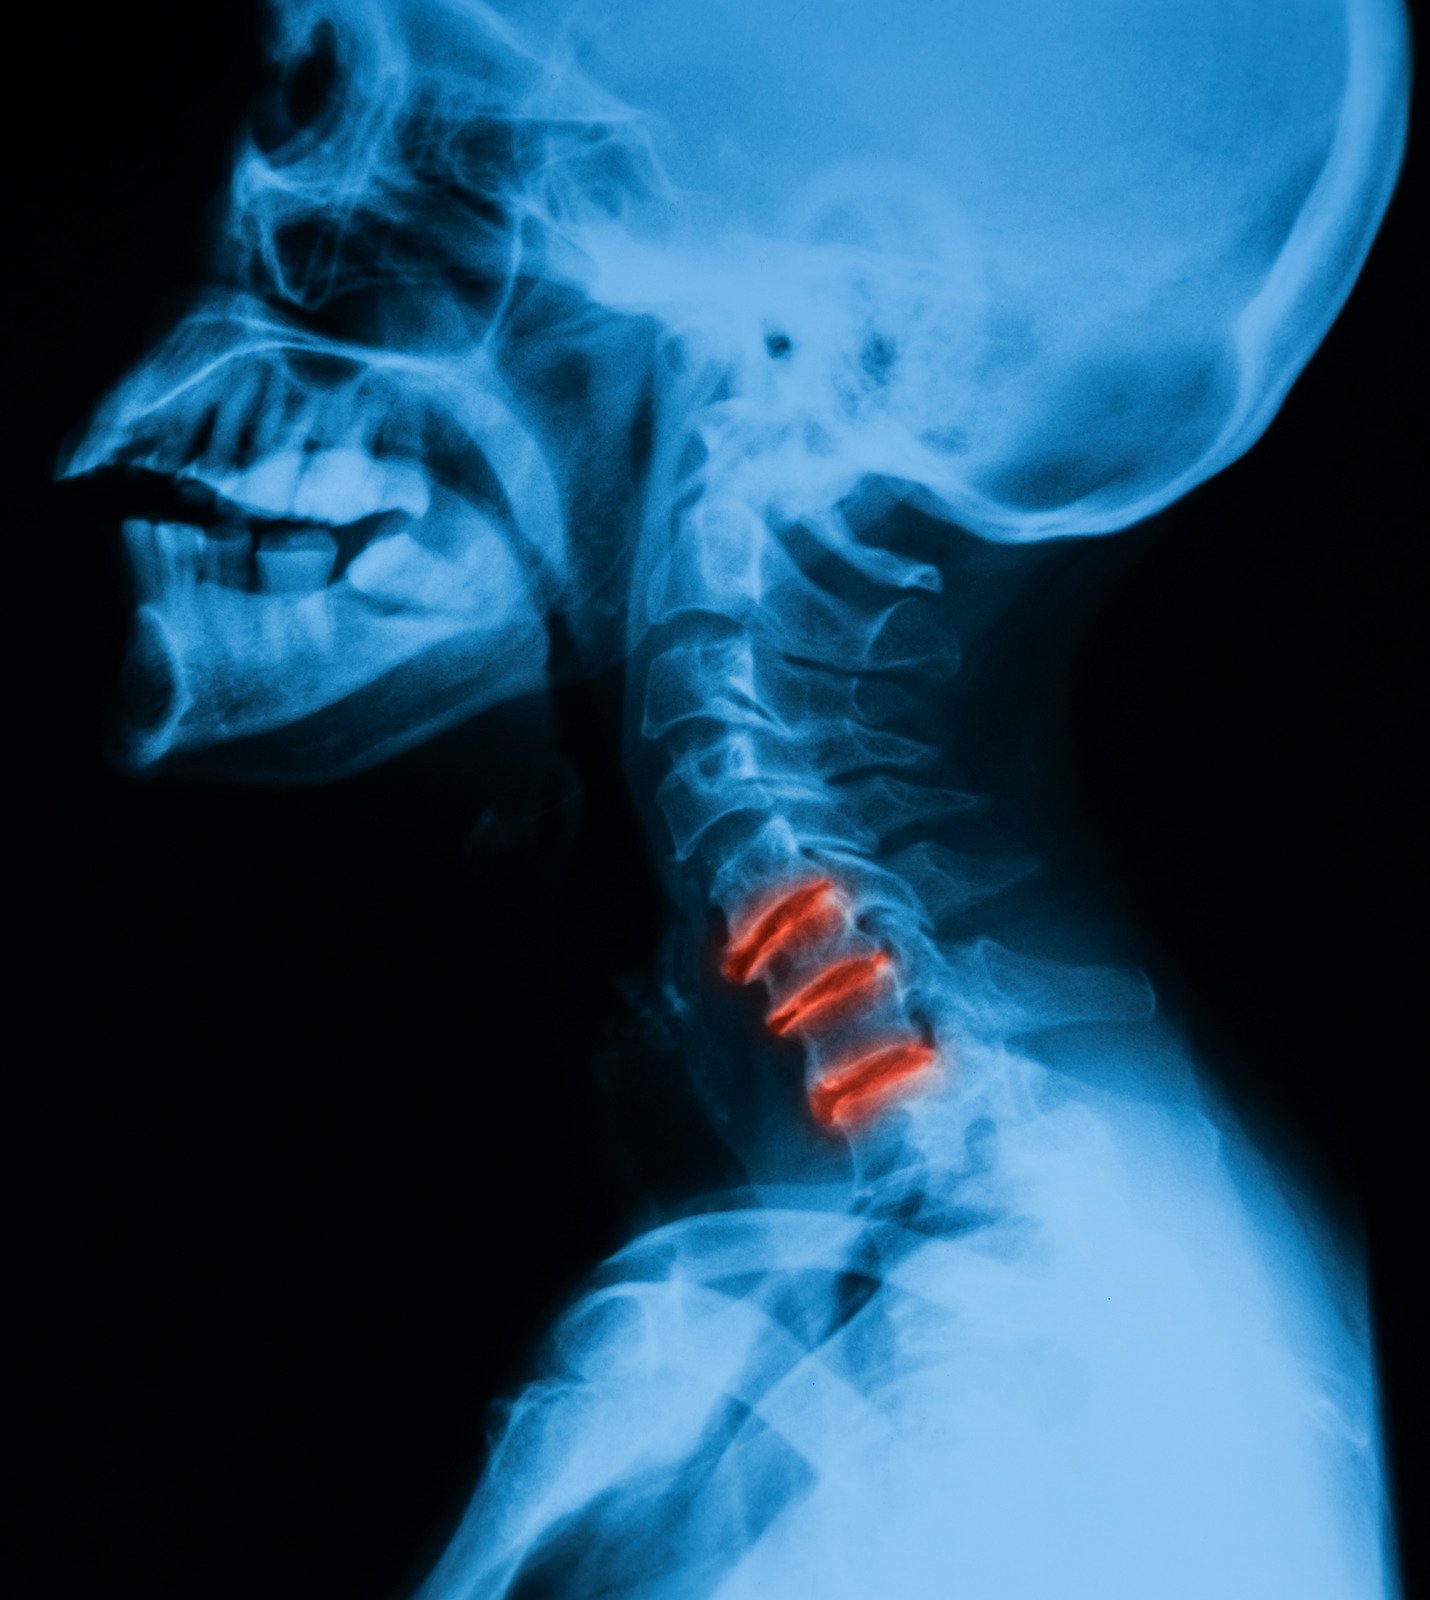

퇴행성 변화: 나이가 들면서 목 디스크나 척추에 퇴행성 변화가 생겨 통증을 유발할 수 있습니다.

수술: 심각한 경우, 특히 신경 압박이나 척추 문제로 인한 목 통증에 대해서는 수술적 치료가 필요할 수 있습니다.